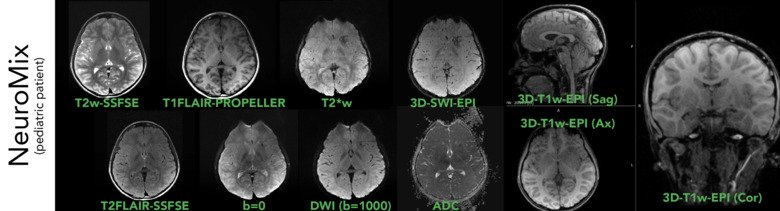

Ultrafast (and motion robust) MR - NeuroMix

Here we show one slice per contrast from NeuroMix on a pediatric patient, as the first scan in our motion robust pediatric MR protocol. With a scan time for NeuroMix of ~2:40 min, where the 2D contrasts are motion robust and can be registered against each other in the reconstruction, these images usually turn out well even in the presence of larger head movements. And with future integration with WRAD & Tracoline, NeuroMix will be even more robust against head motion.